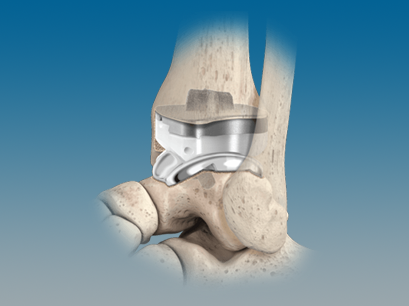

QUANTUM® Total Ankle System with OrthoPlanify™ Patient Specific Instrumentation